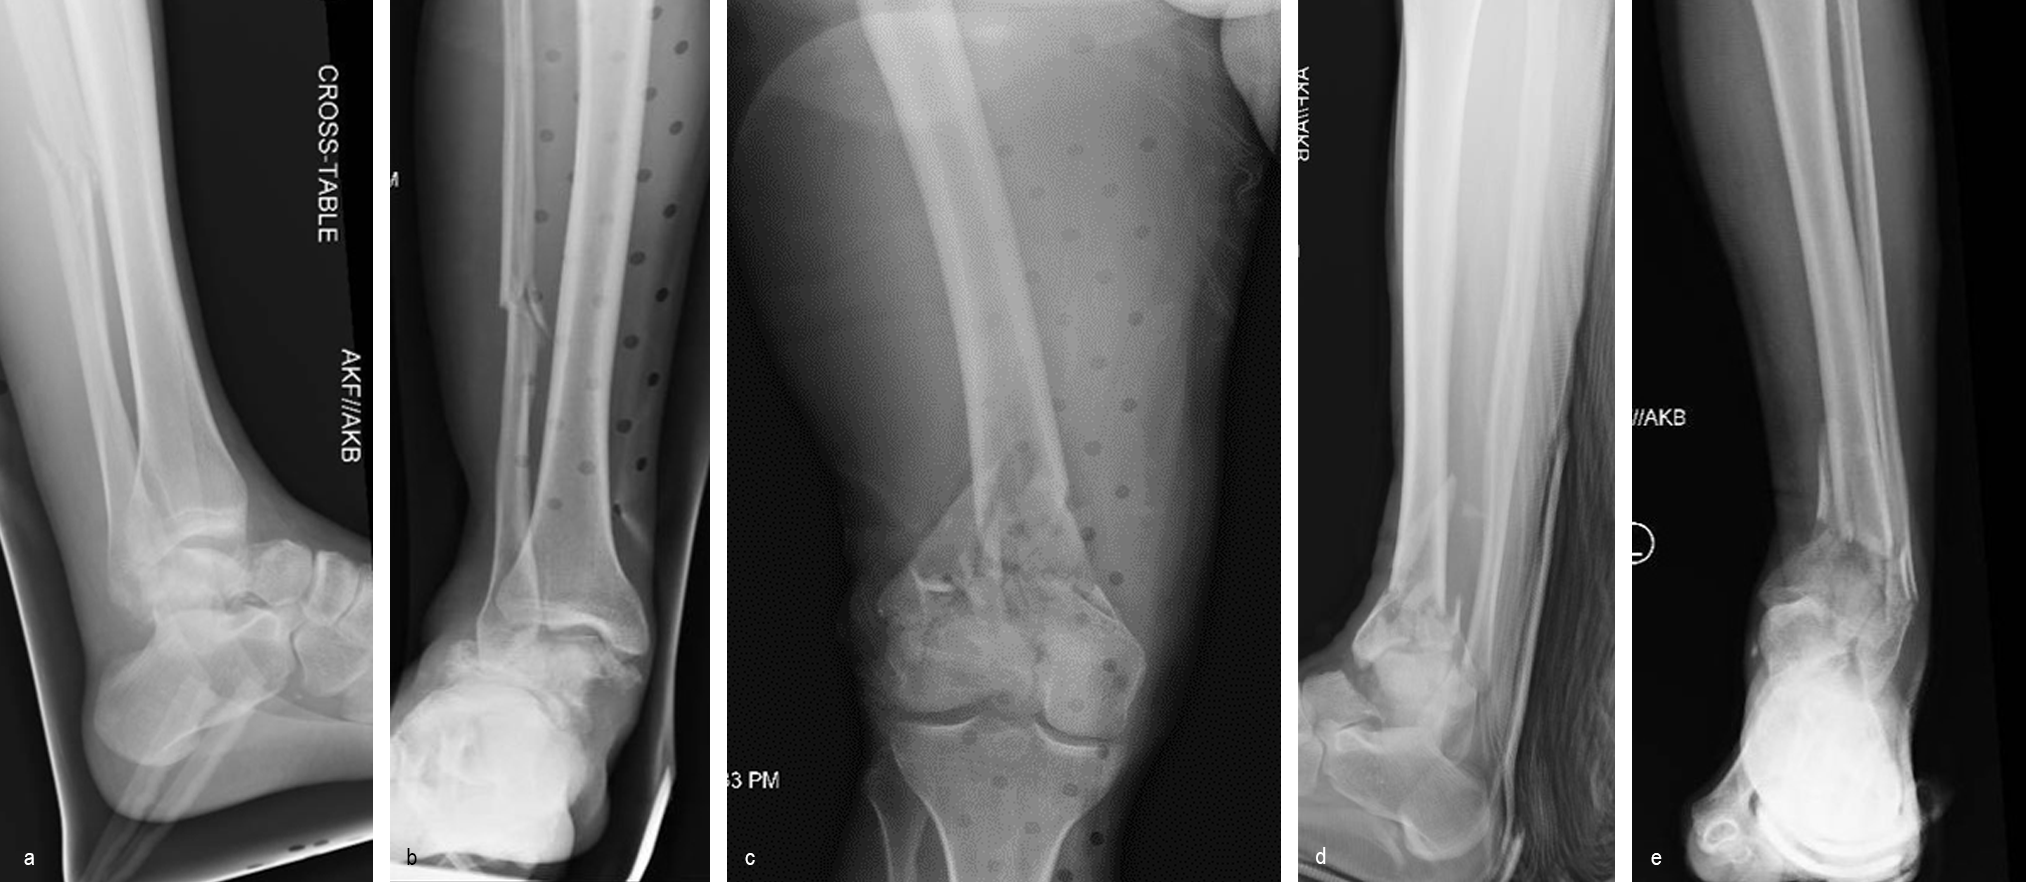

Case 1—Open right supracondylar intracondylar distal femoral fracture following motor vehicle accident

(Case kindly provided by Brent Norris, Orthopedic and Trauma Services of Oklahoma, USA)

A 34-year-old man was involved in a motor vehicle accident in December 2019 and sustained these injuries (Fig 5):

> Left-sided rib fractures with lung contusion

> Open right supracondylar intracondylar distal femoral fracture with possible vascular injury (limb-threatening injury)

> Closed right bimalleolar ankle fracture

> Closed right talar fracture

> Open left plafond fracture

> Open left talar fracture dislocation

> Open left elbow joint

He had no major previous medical history and worked in the furniture delivery business.

The day following admission, the patient underwent these procedures in the operating room (Fig 6):

> Washout of open injuries right side, including femur and ankle

> Open reduction of the talar injury

> Spanning external fixator of the femur and ankle

> External fixation of the left plafond/talus

At 3 days postoperative, the patient underwent a repeat washout of the right femur and right ankle. The lung injury was still recovering so no definitive fixation was performed at this time.

At 5 days post-initial surgery, the lung injury was improved, so the patient underwent open reduction and internal fixation (ORIF) of the right distal femur with resection of devitalized bone and cement spacer placement (Fig 7). Definitive fixation of the other fractures (ankle and ribs) was undertaken over time.